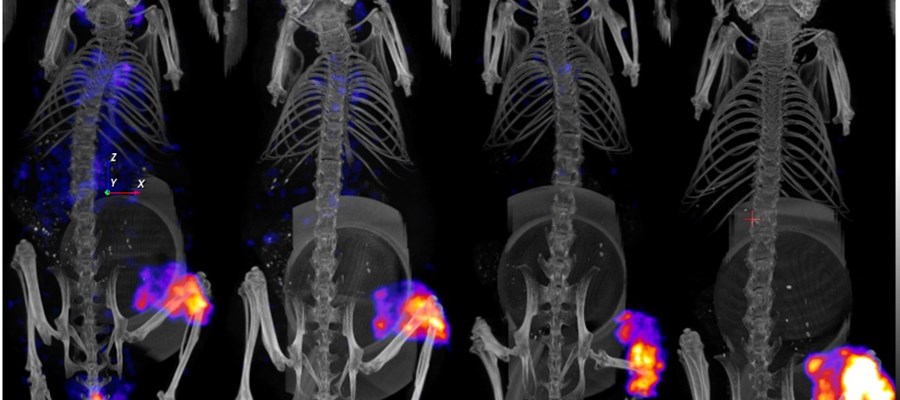

PET/CT-bild av möss (transversal vy) med tumörupptag av Fluor-18.

PET och SPECT-tekniken bygger på att man injicerar en liten mängd radioaktivt ämne i kroppen. Ämnet söker sig till det område i kroppen som forskarna vill studera, till exempel en tumör. Genom att mäta strålningen som ämnet avger kan man få en bild av tumörens storlek, form och hur mycket aktivitet som har tagits upp i tumören.

– Vi kan till exempel studera hur själva substansen tas upp i tumören, genom att jämföra hur mycket av det radioaktiva ämnet som finns i tumören före och efter en viss typ av behandling. Vi mäter strålningen som kommer ut från det radioaktiva ämnet och skapar sedan en tredimensionell bild av hur ämnet tagits upp i kroppen. Att kunna mäta radioaktiviteten med hög noggrannhet är en förutsättning för att kunna utvärdera tumören och avgöra hur väl en viss typ av behandling fungerar, säger Marie Sydoff, forskare vid LBIC.

De nya PET- och SPECT-kamerorna, speciellt utformade för forskning på smådjur, erbjuder betydande förbättringar jämfört med tidigare system. Den höga upplösningen möjliggör visualisering av mindre detaljer och ger en mer precis bild av de fysiologiska processer som man studerar. Kameran är dessutom snabbare och kan avbilda flera djur samtidigt, vilket effektiviserar forskningen och sparar både tid och resurser i form av färre försöksdjur. Den ökade effektiviteten ger även ekonomiska fördelar för forskargrupperna. Dessutom har kameran en förbättrad användarvänlighet som underlättar forskarnas arbete.